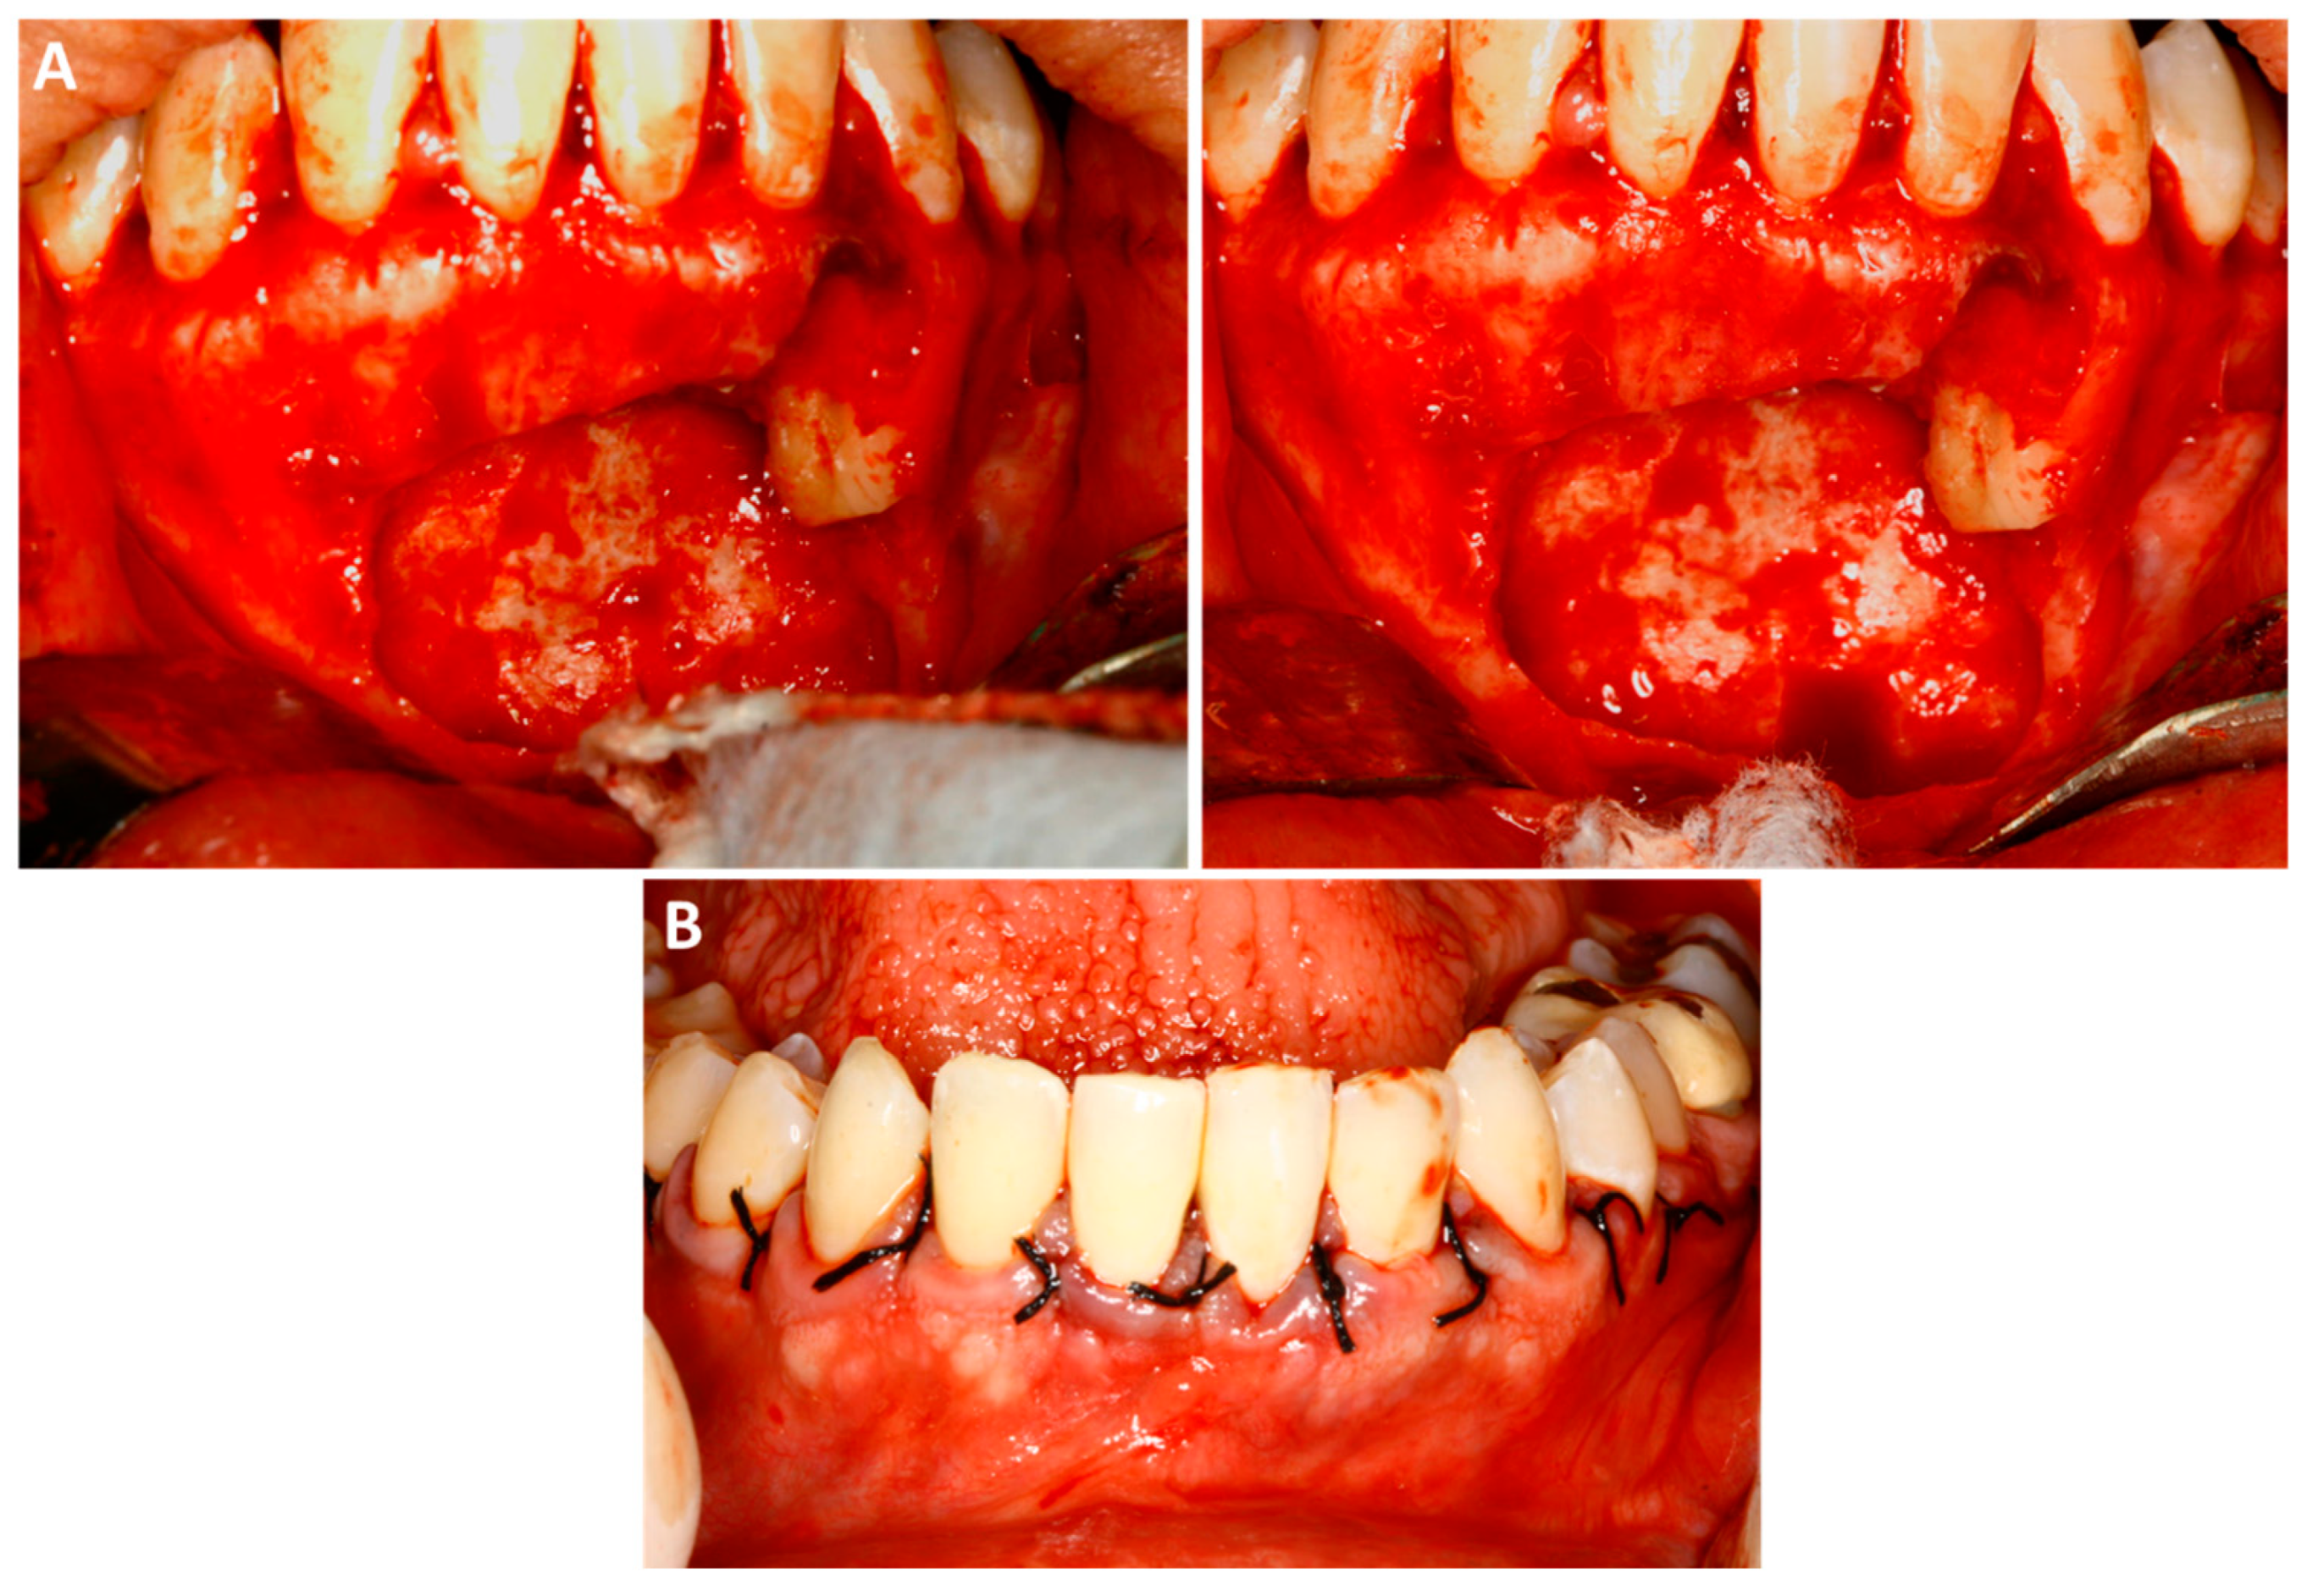

The removal of the lesion was performed under local anesthesia, upon the administration of three anesthetic cartridges of 2% mepivacaine with epinephrine 1:100,000 (Mepiadre, DFL, 1.8 mL, Brazil). An osteotomy was performed in the vestibular cortex to access the lesion (Figure 3A). Following this, after careful curettage, an apicectomy of the involved teeth was performed to access the posterior region of the roots in order to allow a proper peripheral ostectomy at this region of the surgical site. Careful root scaling and planning of the involved teeth were also performed. The closure was done using interrupted sutures (Figure 3B). The entire removed lesion was sent for histopathological examination, which confirmed the diagnosis of GOC.

Figure 3. Trans-operative images of the surgical procedure. (A)—First surgery—the surgical access and the ostectomy were performed via vestibular cortex. (B)—Surgical flap was positioned, and sutures were performed.